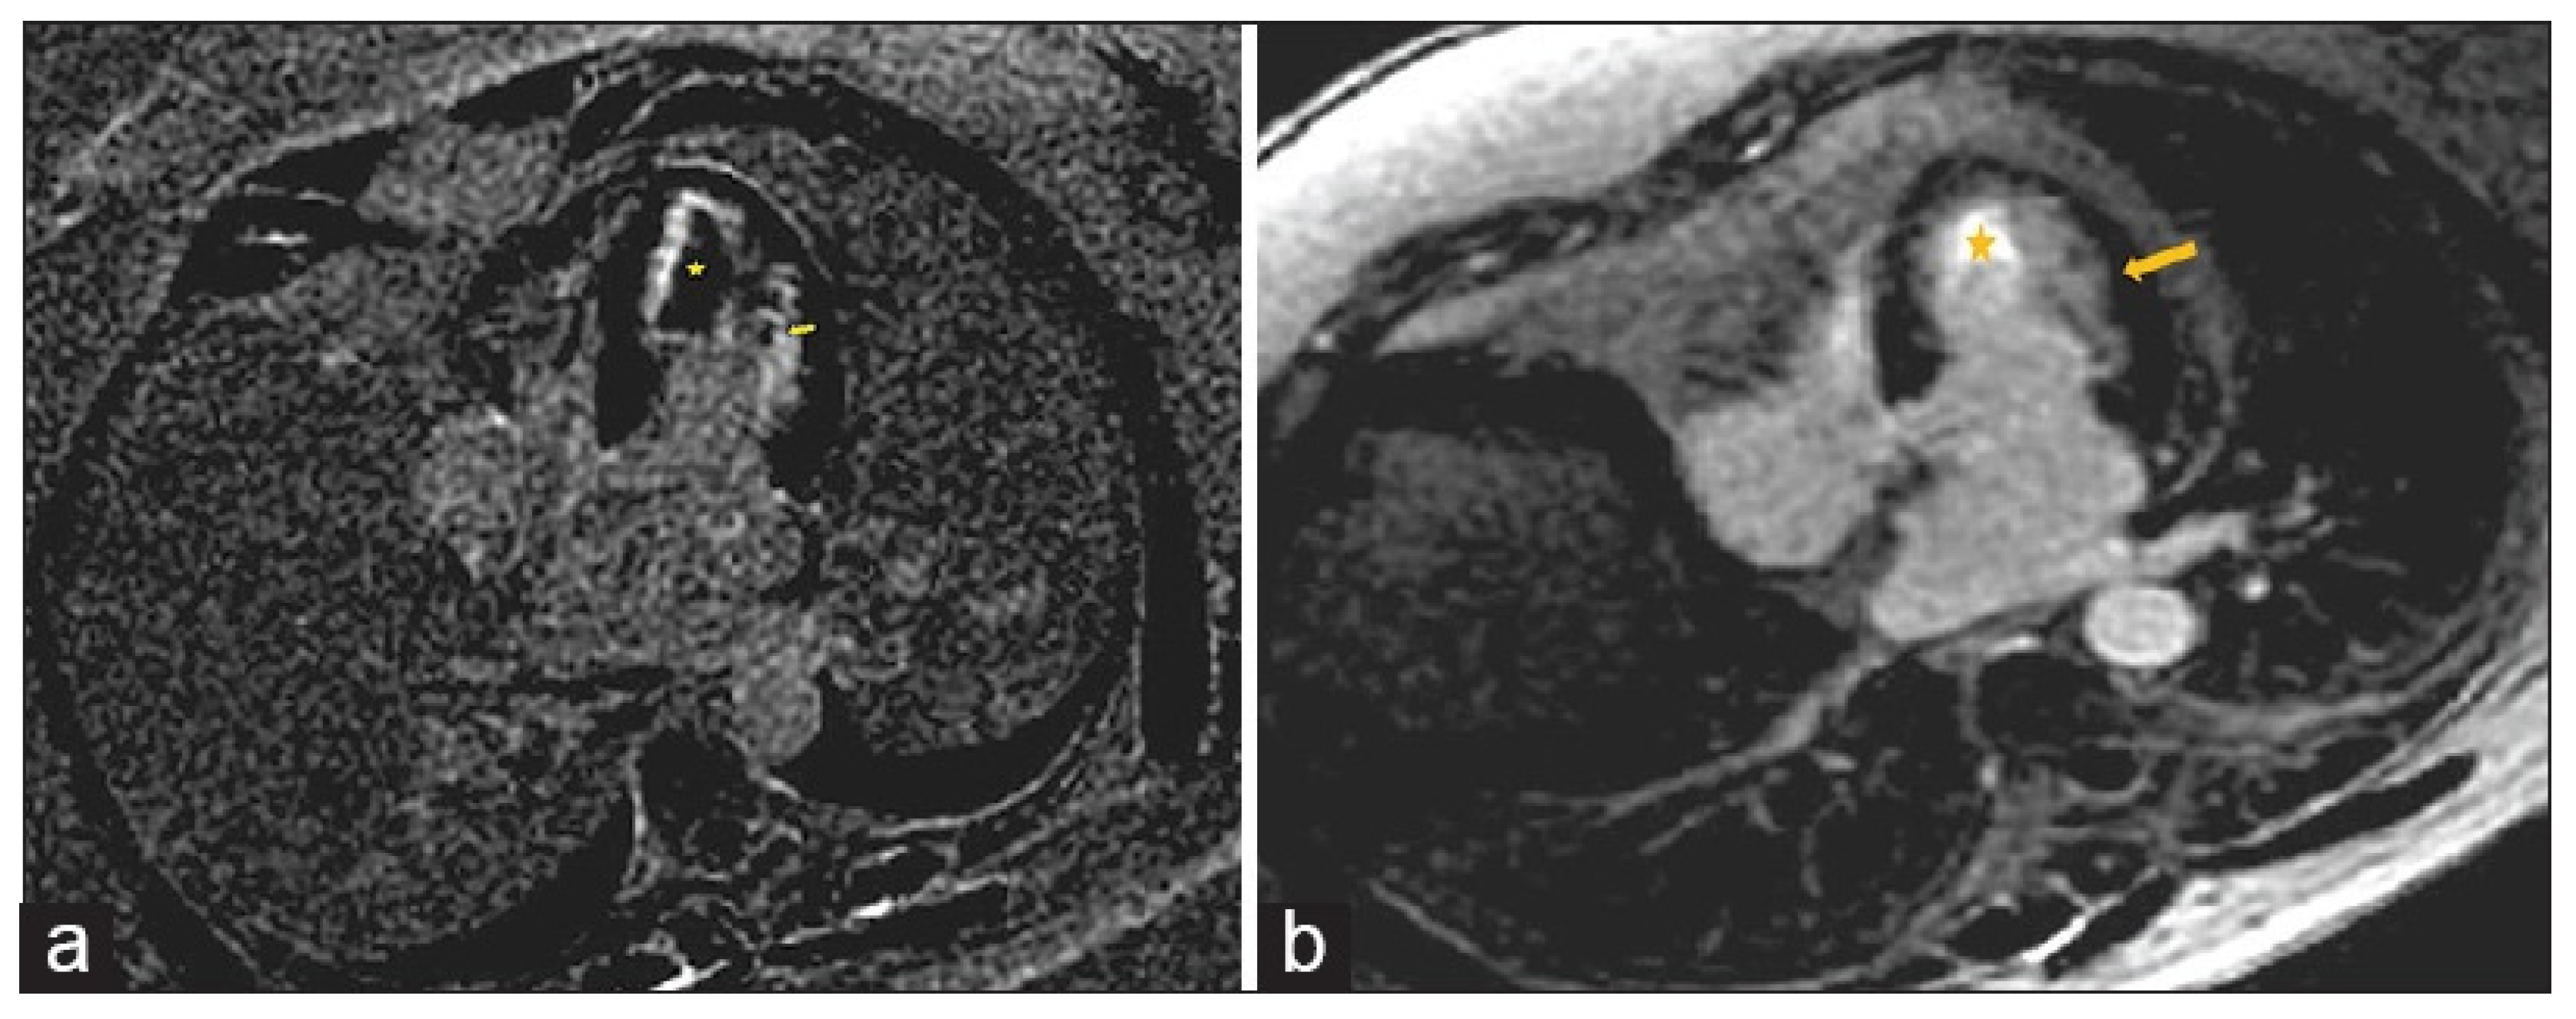

Figure 6.

A 65-year-old female with reduced EF (24%), LV dilation (EDV/BSA: 153 ml/mq), and no significant coronary artery disease. No hyperemia (a, EGE ratio < 4), neither edema (b, T2 ratio < 2) nor LGE (c), was found: oLLC were negative for suspected acute myocarditis. Native T1 was severely increased (d), with a mid-ventricular mean value of 1190 ms; ECV (e) mean value was 35%, and T2 mapping was slightly increased (f, mean value: 52 ms). Both T1 and T2 criteria were positive according to nLLC, and the diagnosis of viral myocarditis was confirmed by EMB. EF—ejection fraction, EDV—end-diastolic volume, BSA—body surface area, EGE—early gadolinium enhancement, STIR—short tau inversion recovery, LGE—late gadolinium enhancement, oLLC—old Lake Louise Criteria, ECV—extracellular volume, nLLC—new Lake Louise Criteria, and EMB—endomyocardial biopsy. Reproduced from: Cundari, G., et al. (2021) [17]. Licensed under CC BY 4.0 (https://creativecommons.org/licenses/by/4.0/ accessed on 15 December 2025).